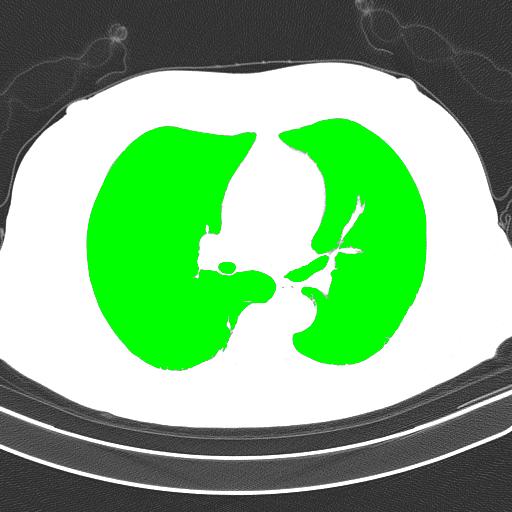

Here is our image processing pipeline visualized step-by-step:

Grayscale -> Otsu's threshold

Detected objects to extract highlighted in green -> Filled mask

Bitwise-and to get our result -> Optional result with white background instead